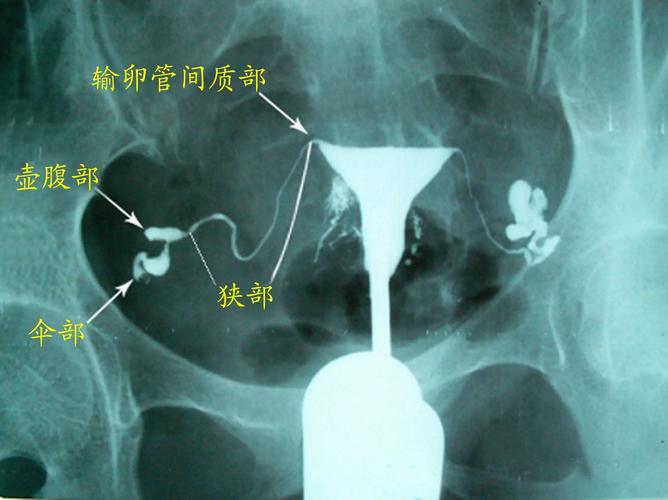

输卵管粘连部位有黏连的情况,或者输卵管伞端粘连,那么建议做输卵管造影检查,检查输卵管是否通畅。